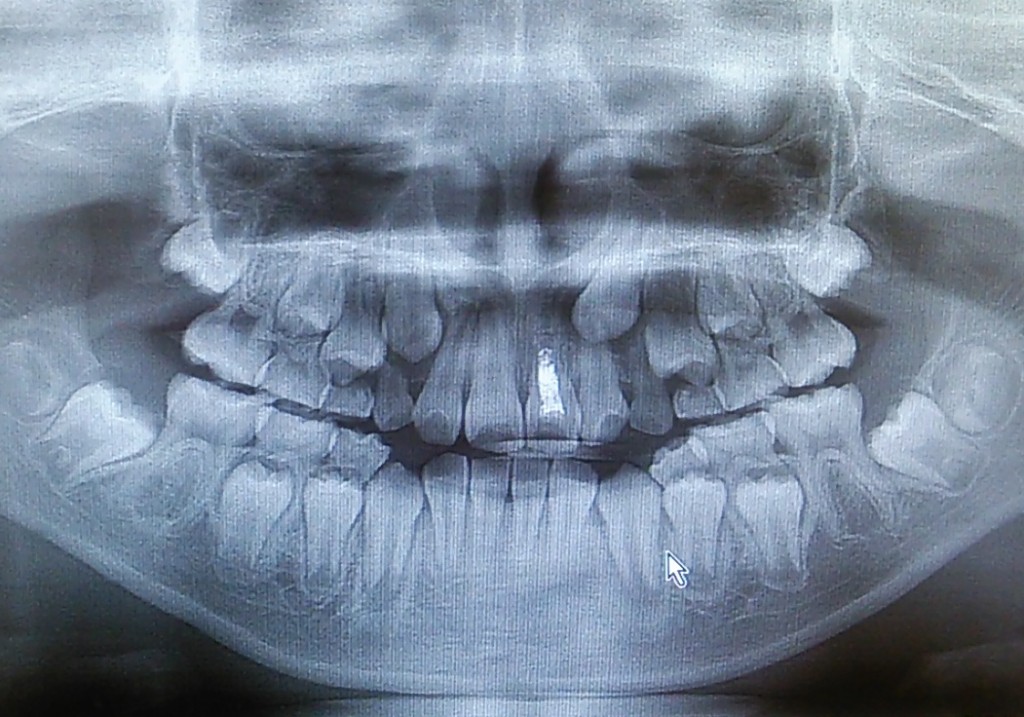

なんと!当院のパノラマレントゲン機器が新しくなりましたー!!!

歯科のレントゲン機器は、目まぐるしく、どんどん性能アップしていきます。

『どこまで鮮明に歯(むし歯)・神経(歯髄)・歯骨が写せるか!?』

これは↑、歯科治療を行ううえでとっても大事なことです。

当院も開院10年が過ぎ、より「丁寧」な治療をご提供できるよう、パノラマレントゲン機器の入れ替えをしました。